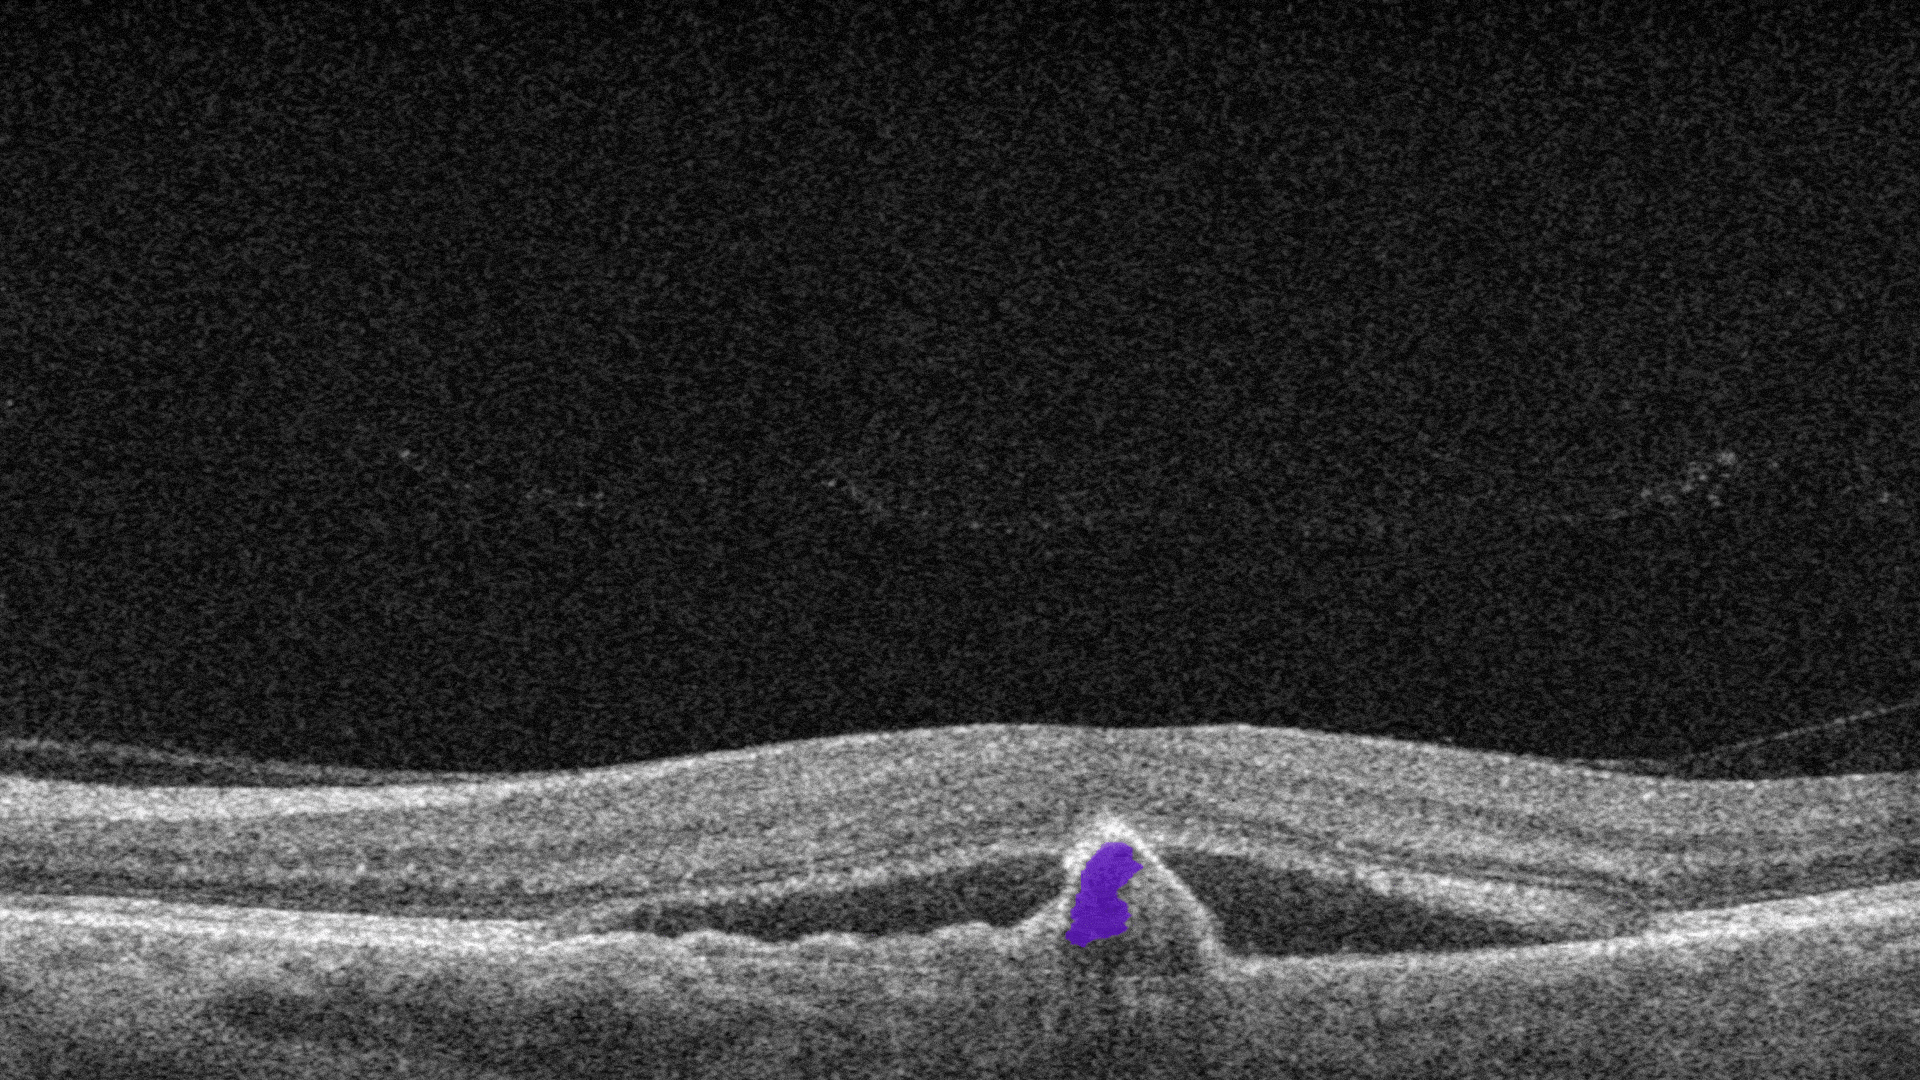

Subretinal fluid corresponds to the accumulation of a clear or lipid-rich exudate (serous fluid) in the subretinal space, i.e., between the neurosensory retina (NSR) and the underlying retinal pigment epithelium (RPE), in the absence of retinal breaks, tears, or traction

-

Fibrovascular RPE detachment. Delamination of the pigment epithelium of the retina is caused by the presence of newly formed vessels (fibrovascular membrane) under the RPE.

Subretinal hyperreflective material (SHRM). It’s a hyperreflective material that is external to the retina and internal to the retinal pigment epithelium (RPE)